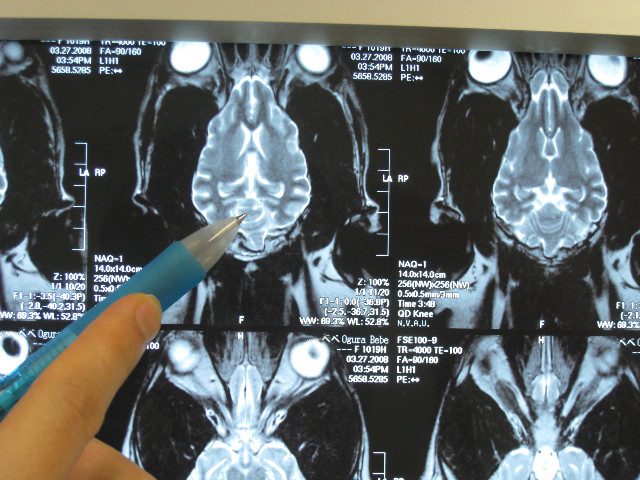

そしてMRIの現像を見せてもらいながら診察結果が告げられた。

【小脳梗塞】です。

脳は左右対称なので、対象ではない箇所があればそれが病変部分なんだって。

(たぶん仰向けに寝て、輪切りに撮ったところ)

梗塞が大きいと、白っぽい点ももっと大きいんだって。

(たぶん仰向けに寝てスライスするように撮ったところ)

こんな小さな病変で立てなくなっちゃうのね....。

でも軽度の梗塞で良かった!

●脳は左右対称である。対象でないところがあればそこが病変箇所である

●べべの病変は真ん中より1〜2ミリ左寄り。(この位置の病変だとマヒは左にでるはず?)